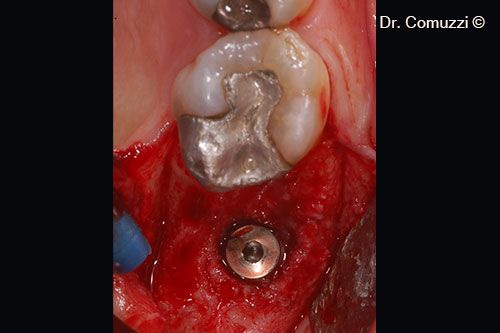

5. Implant position at crest

7. Cover screw application